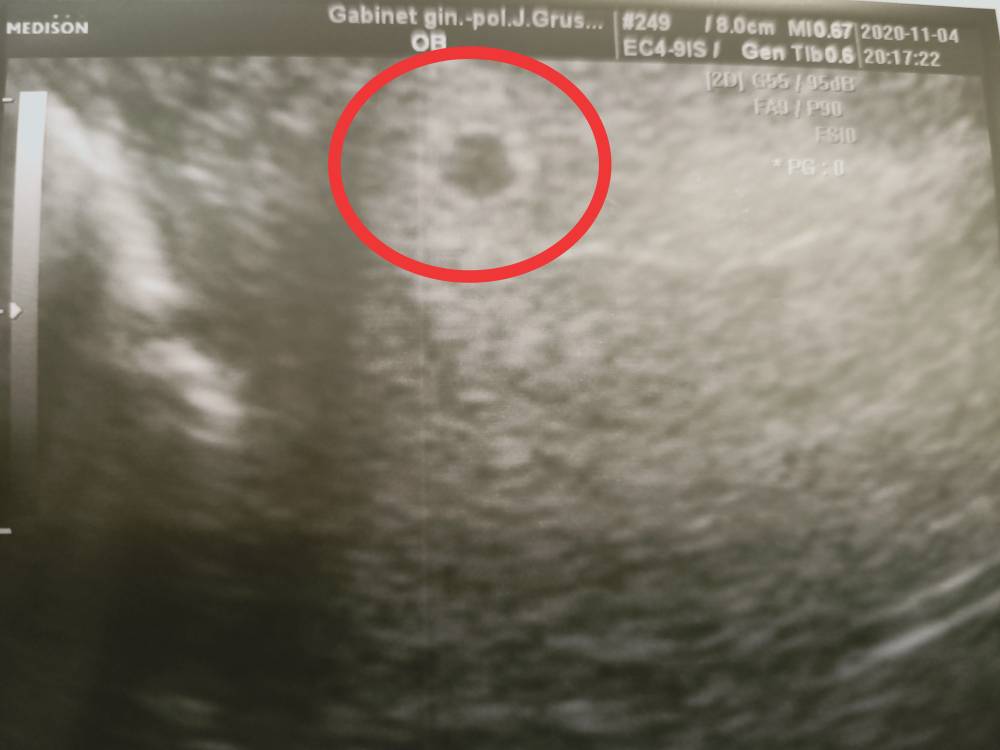

Jest pęcherzyk.

A tu poniżej przedstawiam swój pęcherzyk.Zobacz załącznik 1197211Zobacz załącznik 1197212